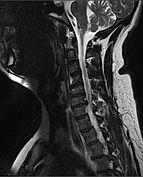

MRI of fractured and dislocated neck vertebra that is compressing the spinal cord | |